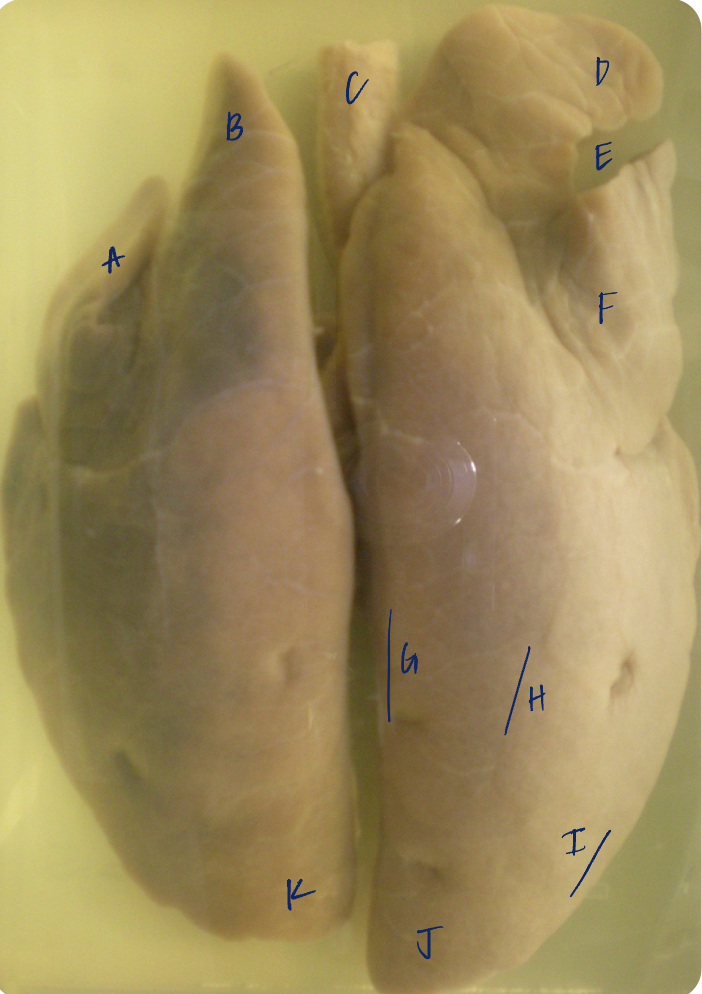

A

(pig lungs, dorsal)

L cranial lobe, caudal segment

B

(pig lungs, dorsal)

L cranial lobe, cranial segment

C

(pig lungs, dorsal)

trachea

D

(pig lungs, dorsal)

R cranial lobe

E

(pig lungs, dorsal)

cardiac notch

F

(pig lungs, dorsal)

middle lobe

G

(pig lungs, dorsal)

dorsal border

H

(pig lungs, dorsal)

costal surface

I

(pig lungs, dorsal)

basal border

J

(pig lungs, dorsal)

R caudal lobe

K

(pig lungs, dorsal)

L caudal lobe

A

(pig lungs, dorsal)

L cranial lobe, caudal segment

B

(pig lungs, dorsal)

L cranial lobe, cranial segment

C

(pig lungs, dorsal)

trachea

D

(pig lungs, dorsal)

R cranial lobe

E

(pig lungs, dorsal)

cardiac notch

F

(pig lungs, dorsal)

middle lobe

G

(pig lungs, dorsal)

dorsal border

H

(pig lungs, dorsal)

costal surface

I

(pig lungs, dorsal)

basal border

J

(pig lungs, dorsal)

R caudal lobe

K

(pig lungs, dorsal)

L caudal lobe